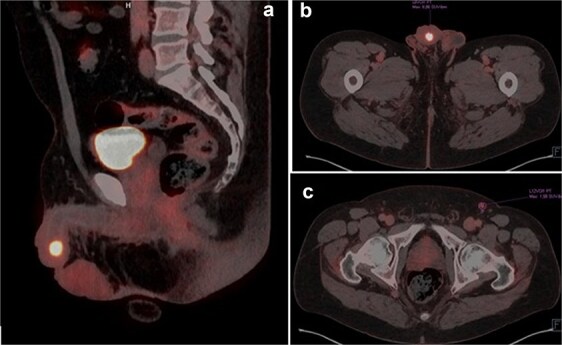

尿道淋巴上皮瘤样癌(LELC)是一种非常罕见的侵袭性肿瘤,目前尚无证据表明其最佳治疗方法。我们提出一个63岁男性诊断为高度尿道LELC的病例,他表现为局部晚期疾病。患者行阴茎部分切除术和双侧腹股沟淋巴结切除术,随后进行全身化疗和免疫治疗。本病例强调了多学科联合手术切除和全身治疗在治疗侵袭性尿道恶性肿瘤中的重要性。鉴于尿道LELC文献的缺乏,额外的病例报告对于增强我们对这种罕见实体的理解和制定循证治疗策略至关重要。

Lymphoepithelioma-like carcinoma (LELC) of the urethra is an exceptionally rare and aggressive neoplasm, with limited evidence available to inform optimal management. We present the case of a 63-year-old male diagnosed with high-grade urethral LELC, who presented with locally advanced disease. The patient underwent partial penectomy with bilateral inguinal lymphadenectomy, followed by systemic chemotherapy and immunotherapy. This case underscores the importance of a multidisciplinary approach combining surgical resection with systemic therapy in the management of aggressive urethral malignancies. Given the paucity of literature on urethral LELC, additional case reports are critical to enhance our understanding and to develop evidence-based treatment strategies for this rare entity.